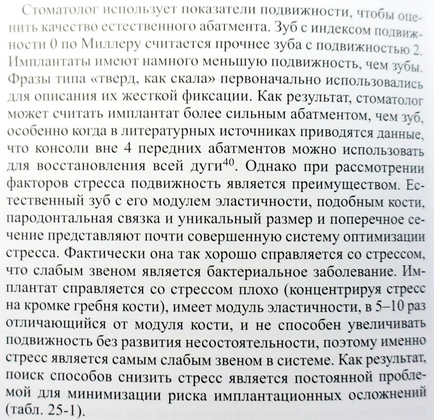

Mielőtt a leírást a második különbség, hogy tisztázni kell egy nagyon fontos pont tekintetében biológiai szélesség (SB).

A „biológiai szélesség” ugyanazt jelenti, mint a fog-fogíny mellékletet. Ahogy közeledik a Apex 3 részből áll:

- Sulkus - sulcus

- epiteliális mellékletet

- kötőszöveti mellékletet

- Biológiai szélessége mintegy fogászati implantátumok és fogorvosi állandó, és körülbelül egyenlő 3 mm. De bárhol implantátumok ez egy kicsit több, mint 3 mm.